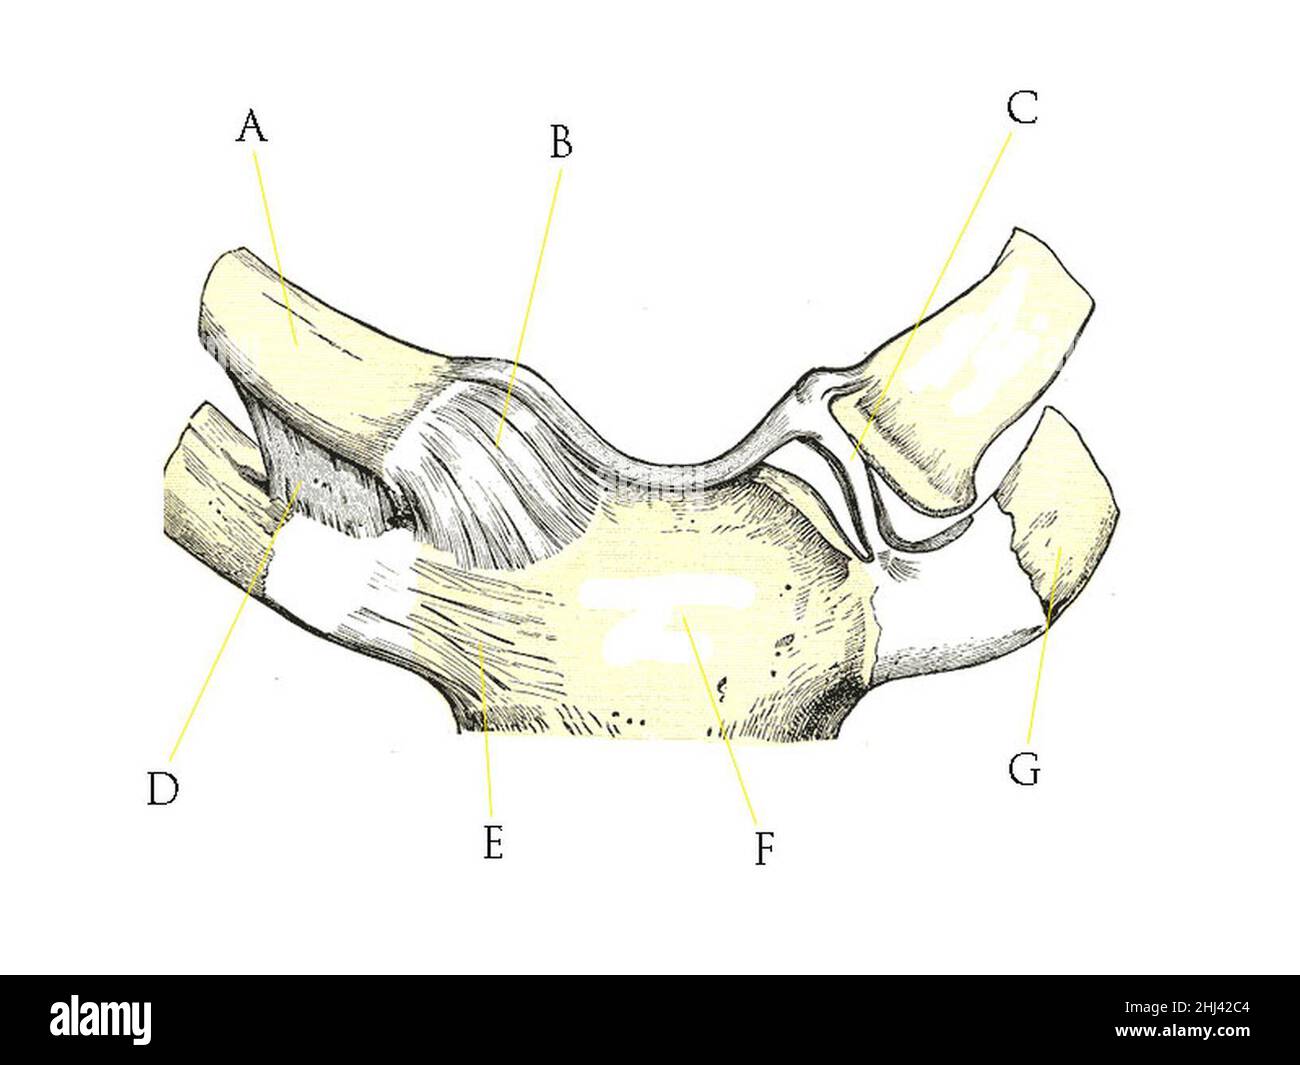

RF3CM31GP–3D-Illustrationskonzept der Anatomie der Knochengelenke der oberen Extremitäten des menschlichen Skelettsystems

RF3CM2YY5–3D-Illustrationskonzept der Anatomie der Knochengelenke der oberen Extremitäten des menschlichen Skelettsystems